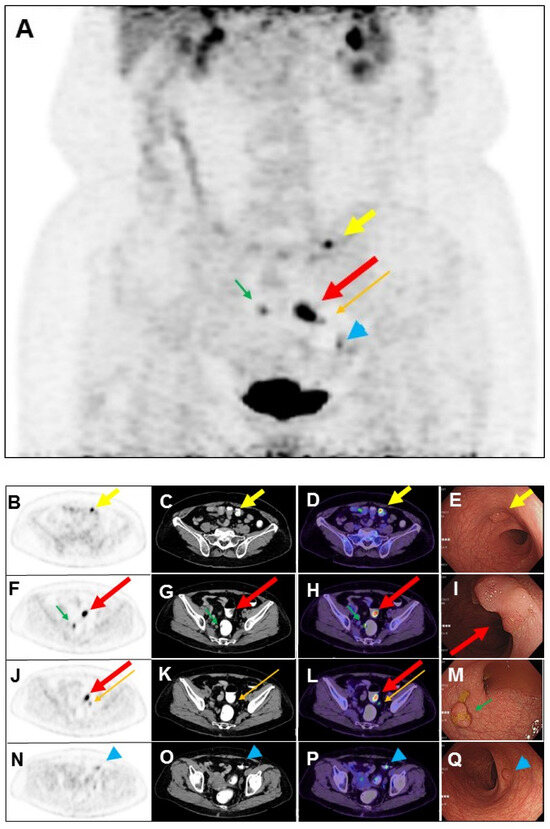

The use of a laxative-augmented contrast medium before a delayed FDG PET/CT scan leads to a reduction in the number of false-positive findings and increases the accuracy in the detection of colorectal cancer [1,2]. Maximum-intensity projection (A), transaxial PET, CT, and fused PET/CT images of delayed FDG PET/CT scan after per-rectal administration of laxative-augmented contrast medium revealed a filling defect with persistent intense FDG uptake in the sigmoid colon (1.8 × 1.8 × 0.6 cm; (A,F,G,H,J,L); long thick arrow), suggesting a hypermetabolic space-occupying lesion in bowel lumen. Further colonoscopy ((I), long thick arrow: red color) revealed a tumor in the sigmoid colon, which was proved to be adenocarcinoma. In addition, hypermetabolic nodule with filling defect in the transverse colon (1 × 0.8 × 0.5 cm; (A–D); short thick arrow) and rectum (1.3 × 0.8 × 0.6 cm; (A,F,G,H); short thin arrow: green color), colonoscopy, and histopathology revealed tubular adenoma and tubulovillous adenoma ((E), short thick arrow: yellow color; (M), short thin arrow: green color), respectively. Another focal mild hypermetabolic nodule in the descending colon (1 × 0.8 × 0.4 cm; (A,N,O,P); arrowhead: blue color) was also noted. The colonoscopy ((Q), arrowhead: blue color) and histopathology revealed tubulovillous adenoma. Later, the patient received laparoscopic anterior resection, and histopathology revealed moderately differentiated adenocarcinoma (2.0 × 2.0 × 0.6 cm) in stage pT1N1b. Lymph nodes had one metastasis to the pericolic ((A,J,K,L); long thin arrow: orange color) and inferior mesentery artery regions, respectively. Colorectal cancer is the third-leading cause of cancer death in the world [3]. Colorectal cancer usually begins with the most common form: an adenoma that originated from granular cells [4]. The proportion of colon adenoma to adenocarcinoma detected by FDG PET/CT scan is about 73% to 27% [5]. FDG PET is a sensitive imaging method for the detection of colorectal malignancy. However, benign, infectious, inflammatory, and granulomatous processes may also cause an increase in FDG uptake. Delayed FDG PET/CT performed after administration of a laxative-augmented contrast medium might be useful for identifying patients needing additional diagnostic procedures or avoiding unnecessary colonoscopic evaluation. The protocol consists of an initial phosphosoda enema (Fleet; C.B. Fleet, Lynchburg, VA, USA). Following the evacuation, 500 mL of diluted 3% contrast medium (Conray, iothalamate meglumine USP 60%; Mallinckrodt Inc., St Louis, MO, USA) is instilled into the anus. In this case, we used per-rectal administration of laxative-augmented contrast medium, and the detection of adenomas number was increased. An FDG-avid filling defect, suggesting hypermetabolic nodule with the space-occupying lesion, was discovered in an FDG PET/CT scan.